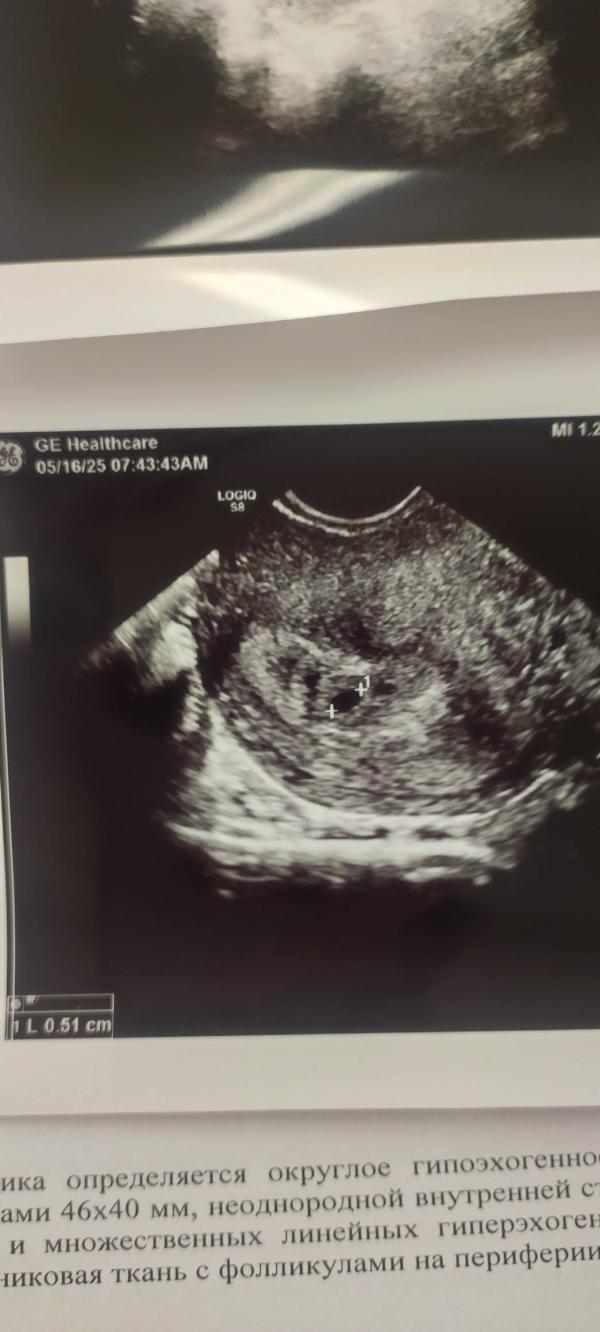

16.05, посещение гинеколога, УЗИ. Беременность маточная, ура! Плодное яйцо 5мм пока без эмбриона и сердцебиения. Прийти на контроль через 2 недели. Аааааа как же дождаться. Как это сложно ждать...

Есть кисты на яичниках, папаверин на 10 дней. Ждать УЗИ. Ждать...